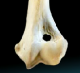

As the photo at the right shows, the condyle has two large rounded ridges -- the medial aspect, which is closest to the dog's torso, and the lateral aspect, which is farthest from the torso. In the photo, the medial aspect is the ridge on the left and the lateral aspect is the ridge on the right. The small part of that knuckle which connects the median and lateral aspects of the condyle is called the trochlea, and the hole above the trochlea and between the median and lateral aspects is called the supratrochlear foramen or just the foramen.